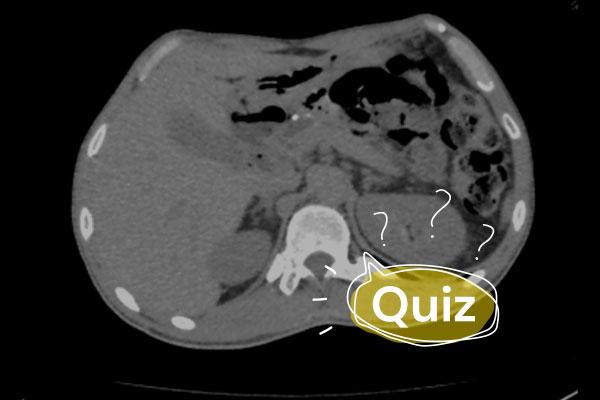

Paciente de 40 anos comparece à emergência queixando-se de dificuldade progressiva em marcha, dores intensas em membros inferiores, zumbido e incontinência urinária há seis meses.

Ele tinha uma carga viral HIV completamente suprimida e uma contagem de CD4 + de 400 células por milímetro cúbico, em vigência de terapia anti-retroviral. Todo exame físico foi realizado e o médico notou uma alteração pupilar curiosa: as pupilas não eram reativas à luz, mas rapidamente se contraiam ao focar um objeto próximo.

Qual sua principal hipótese diagnóstica?

CTabes dorsalis